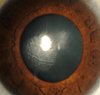

Results: Primary interface complications include infectious keratitis, diffuse lamellar keratitis, central toxic keratopathy, pressure-induced stromal keratopathy (PISK), and epithelial ingrowth. Infectious keratitis is most commonly caused by Methicillin-resistant Staphylococcus aureus (early onset) or atypical Mycobacterium (late onset) postoperatively, and immediate treatment includes flap lift and irrigation, cultures, and initiation of broad-spectrum topical antibiotics, with possible flap amputation for recalcitrant cases. Diffuse lamellar keratitis is a white blood cell infiltrate that appears within the first 5 days postoperatively and is acutely responsive to aggressive topical and oral steroid use in the early stages, but may require flap lift and irrigation to prevent flap necrosis if inflammation worsens. In contrast, PISK is caused by acute steroid response and resolves only with cessation of steroid use and intraocular pressure lowering. Without appropriate therapy PISK can result in severe optic nerve damage. Central toxic keratopathy mimics stage 4 diffuse lamellar keratitis, but occurs early in the postoperative period and is noninflammatory. Observation is the only effective treatment, and flap lift is usually not warranted. Epithelial ingrowth is easily distinguishable from other interface complications and may be self-limited or require flap lift to treat irregular astigmatism and prevent flap melt.